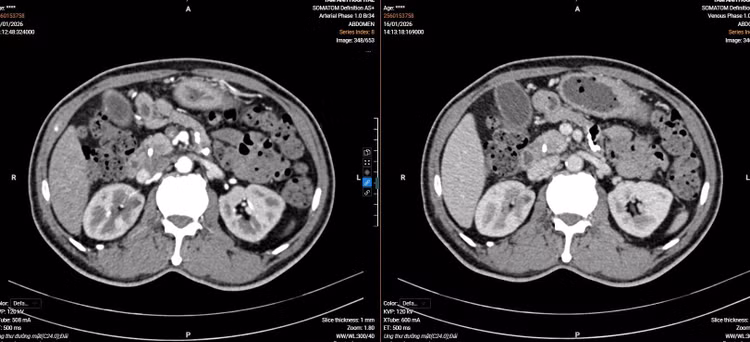

Kết quả cắt lớp vi tính của người bệnh - Ảnh BVCC

ut-bang-quang-1.jpg